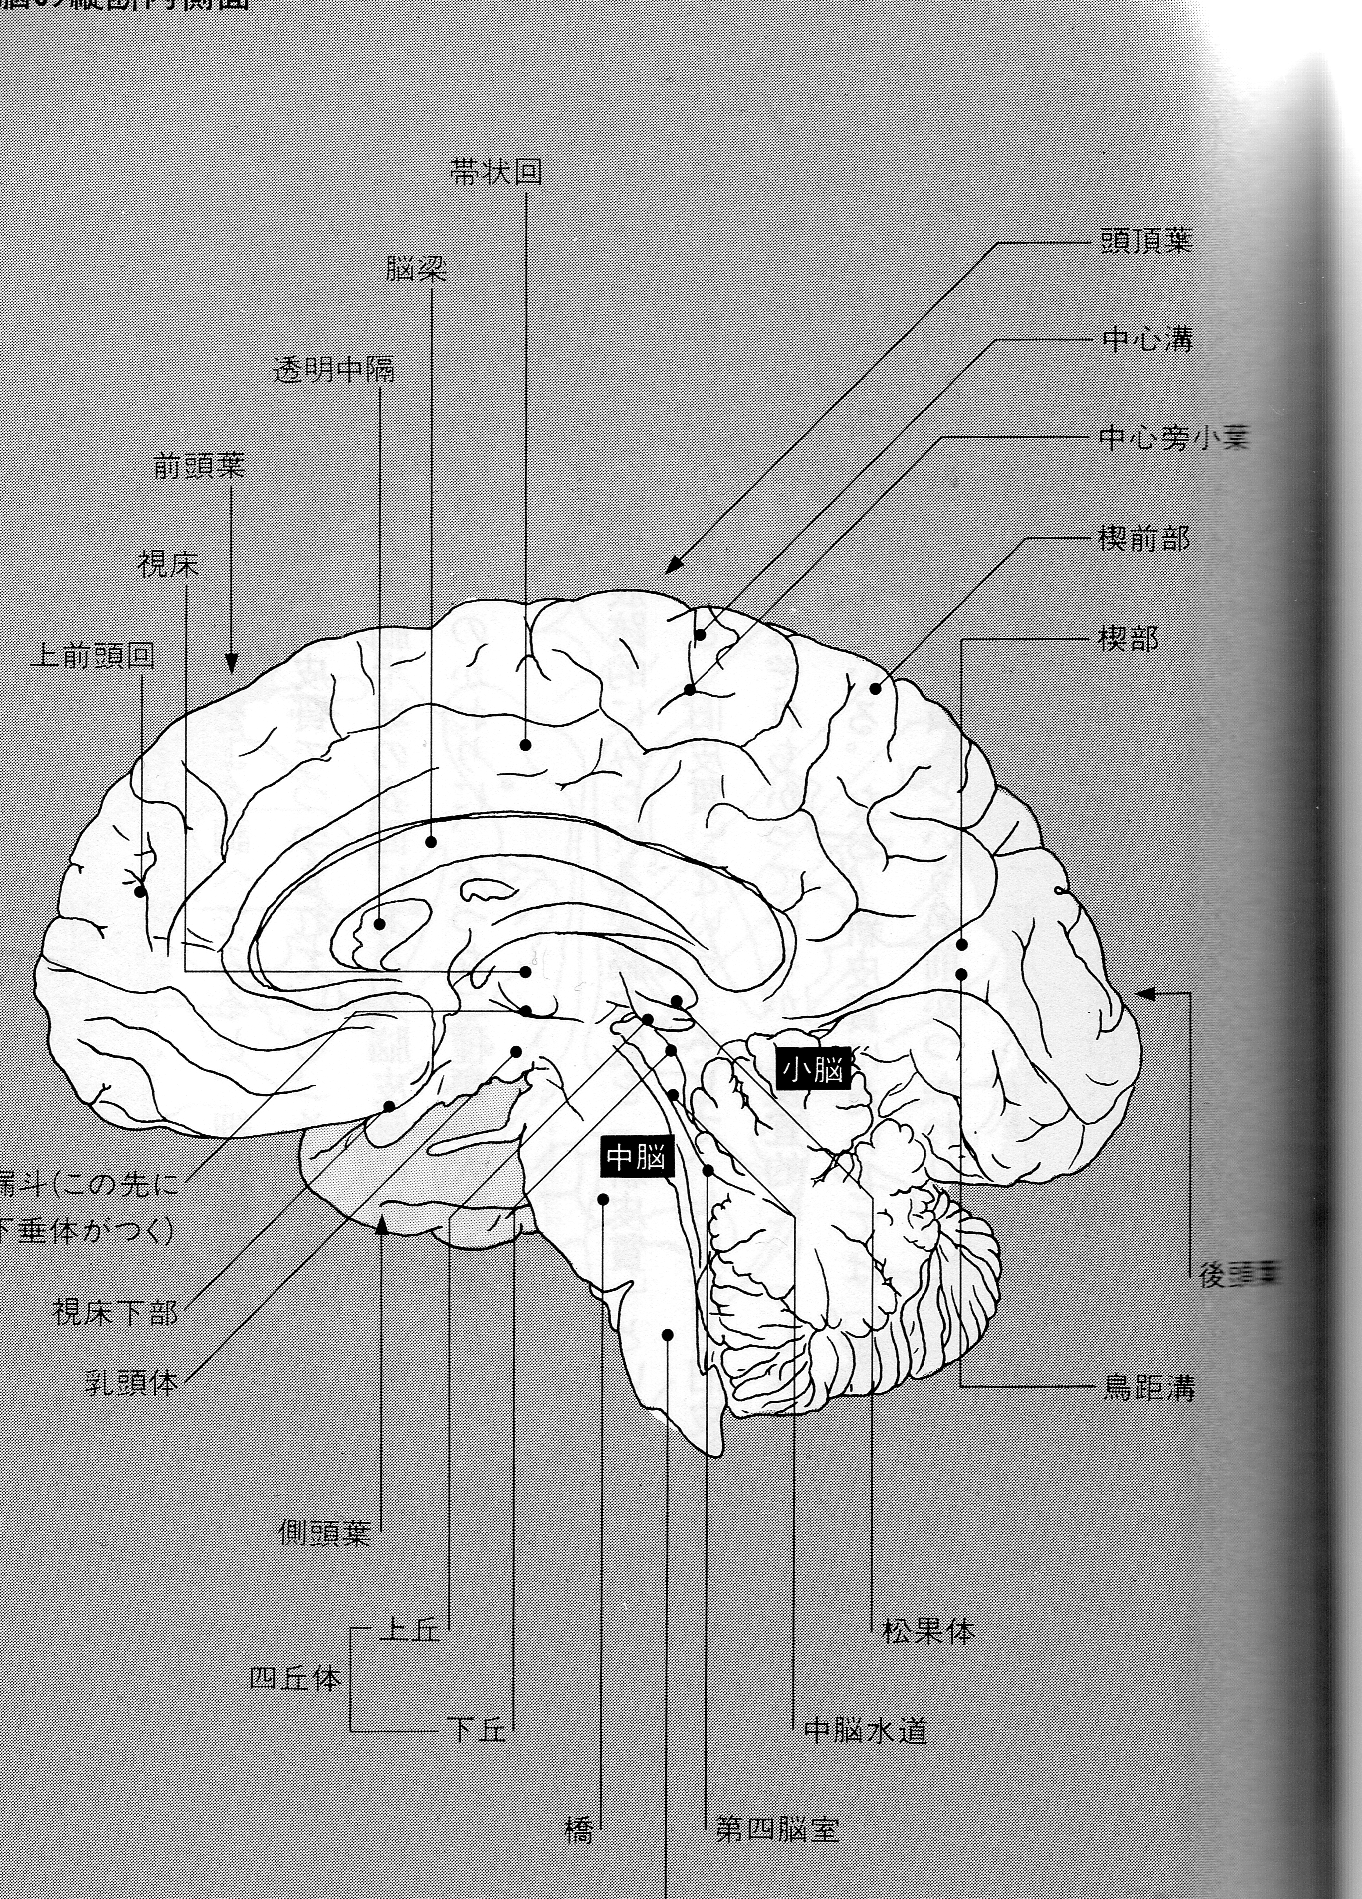

私がさきの章で内分泌腺の機構について図までかかげて説明したのは、これを知ってほしいた めであった。 専門学者はさぞかし片はらいたく思われるのにちがいなかろう。それを承知でおく めんもなく素人の私があえてそれをしたのは、この視床下部の秘密を読者に知ってほしいためで あった。図 を見ればわかる通り、すべての内分泌腺を統御しているのは視床下部である。

そしてここが、ヨーガでいうプラーマ・ランドラの座)であり、サハスララ・チャクラなので ある。今までのヨーガの指導者のいうように、それは、松果腺、松果体ではない。 視床下部が、 サハスララ・チャクラなのである。もっとも、視床下部のすぐそばに松果体があるので、それを あやまったのであろう。もっとも、松果体自身もある重要な役わりを受けもつ。けれども、サ ハスララ・チャクラそのものは松果腺ではなく、視床下部であった。

視床下部はいまいったように、下垂体系を通じて全内分泌器官を統御する。 それでは、なにを もってするのかというと、もちろんそれは神経” である。 したがって視床下部には重要な 神経がたくさん集まっている。 私は、古代ヨーガのなかから、この部分を動かすポーズとムドラ 創案してここにつよい圧力をくわえ、同時に、強烈な思念(念力)を集中していた。百日の あいだ、たえまなく、私はここに、物質的、精神的、両面にわたるつよいエネルギーを集中し た。その結果、ここの神経線維に一大異変が生じたのだ。 その異変により、神経線維が異常 分泌をおこしたか、それともそこにある 変化がおきたのか、そのいずれである

かはわからぬが、それらの分泌液が複雑に混合し合って、化学反応をおこしたのだ。あの火は、 その化学反応による衝撃が、視床の神経をはげしく打って、膜に光を走らせたのだ。 その ここの神経線維にシナプスをむすび、その火はいつでも私の思うまま私の脳の内奥に明星を またたかせることとなった。同時に私の脳の構造も一変した。 求聞持聡明法の成就である。 聞 用法とは、脳の内部の化学反応による脳組織変革であったのだ。

では、視床下部の機構を生理学的にみてみよう。(図説・内分病への手引・土屋雅、他者による) 解剖

視床下部は間脳の一部で、視床にある。

視床下部は体温、循環、新陳代謝、外分泌、平滑筋などの諸機能の調節をつかさどるほかに、 内分泌腺の御の場として重視されている。 調節機序としては、神経性調節(交感

下垂体後葉のバゾプレシン、オキシトシンが視床下部の視索上核や室旁核の神経分泌により支 配されていることが示され、最近は下垂体前葉が次に記すような各種の分泌促進因子 releasing factor の支配下にあることが知られてきた次の図参照)。

In the previous chapter, I explained the mechanism of the endocrine glands with diagrams because I want you to know this. I am sure that specialists would want to pay for it. He knew that, but he did it because I wanted the reader to know the secret of the hypothalamus. As can be seen from the figure, the hypothalamus controls all endocrine glands.

And this is the seat of Prama Randra in yoga), the Sahasrara Chakra, so he exists. It is not the pineal gland or the pineal gland, as some yoga teachers have said. The hypothalamus is the sahasrara chakra. However, since the pineal gland is located right next to the hypothalamus, he must have made a mistake. However, the pineal gland itself also has an important role to play. However, his Hasrara chakra itself was not the pineal gland, but the hypothalamus.

The hypothalamus once again controls all endocrine organs through the pituitary system. Of course, it is nerves. Therefore, many important nerves are concentrated in the hypothalamus. At the same time, I was exerting a strong pressure on this place, and at the same time, I was concentrating a strong thought (telekinetic power) on it. As a result, there was a major change in the nerve fibers here.

I don’t know why, but those secretions mixed in a complicated way and caused a chemical reaction. That fire, the impact of the chemical reaction, hit the nerves of the thalamus violently, causing light to run through the membrane. He made a synapse with the nerve fibers here, and that fire would make the stars twinkle in the depths of my brain whenever I wanted to. At the same time, the structure of my brain changed completely. It is the fulfillment of the Inquisition, Acquisition, and Wisdom Law. Listening is a change in brain tissue due to chemical reactions inside the brain.